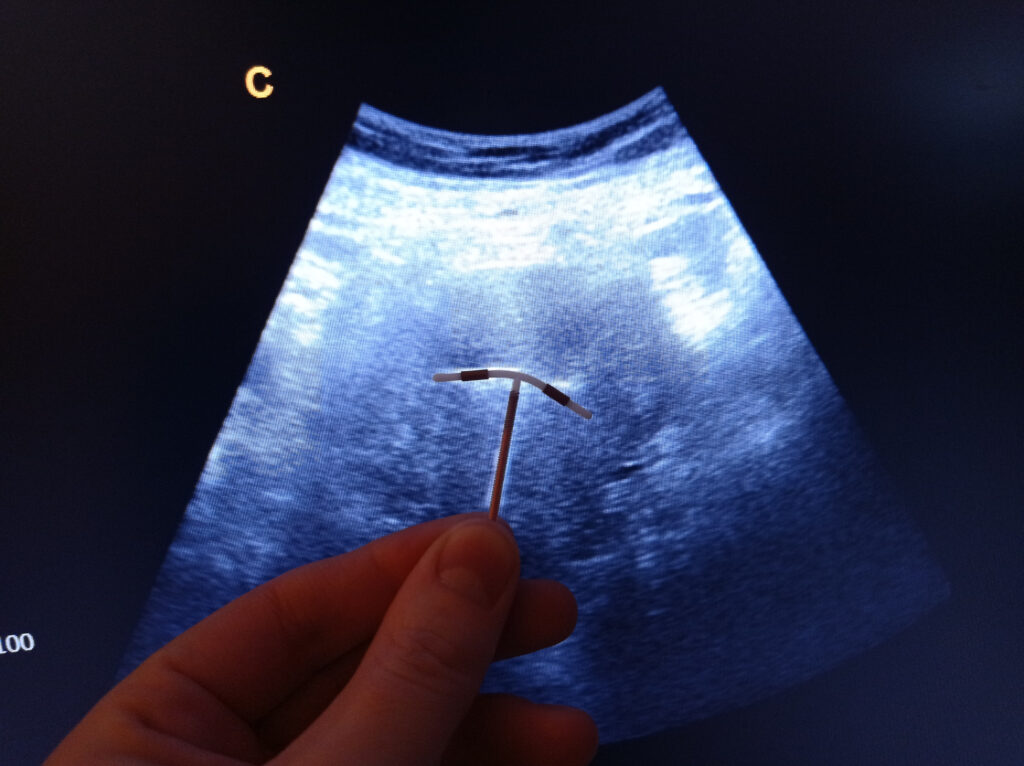

Antes de nos aprofundarmos na questão da gravidez com DIU, vale a pena entender o que é esse pequeno dispositivo e como ele age no nosso corpo. O DIU, ou Dispositivo Intrauterino, é uma pequena peça em forma de “T” que é inserida no útero por um profissional de saúde. Ele pode ser feito de cobre ou liberar hormônios, como o levonorgestrel.

O Papel do Ultrassom

O ultrassom é uma ferramenta essencial para verificar a posição do DIU. Ele não só confirma se o DIU está no lugar certo após a inserção, como também pode ser usado para verificar se tudo continua bem ao longo do tempo.

Agora, quanto à frequência desse controle. Geralmente, um ultrassom é recomendado imediatamente após a inserção do DIU e depois, em revisões anuais. Mas se você sentir algum desconforto ou outros sintomas estranhos, não hesite em conversar com seu médico pois ele poderá pedir um exame extra.

Lembre-se, se você está experimentando algum desses sintomas, o melhor é marcar uma consulta com seu médico para um exame de ultrassom ou raio-X. Esses métodos vão confirmar a posição do seu DIU e permitir que qualquer problema seja corrigido o mais rápido possível.

1. Consultar o Médico: Se você suspeita que seu DIU saiu do lugar, marque uma consulta o quanto antes. Um exame de ultrassom vai confirmar o diagnóstico.